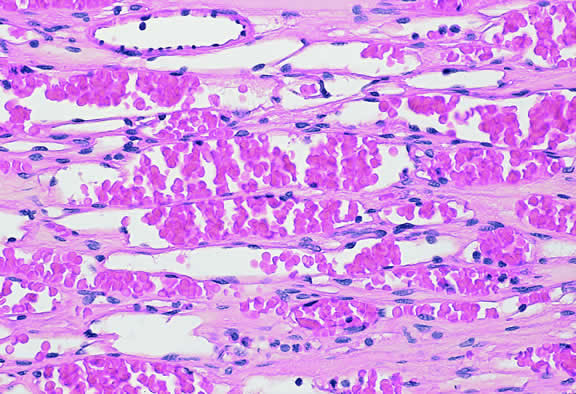

Leukemia

Secondary ocular involvement is relatively common in patients with advanced leukemia; Leonardy and coworkers199 found ocular involvement in 31% of 135 eyes obtained postmortem from leukemic patients. Ocular tissues may involved primarily by infiltrates of leukemic cells or secondarily by manifestations of the disease including hemorrhage, ischemia, or secondary infection related to primary immunosuppression or the effect of immunosuppressive drugs.200,201 Although leukemic cells can infiltrate almost any ocular tissue, choroidal infiltration occurs most often. Kinkaid and Green201 found some degree of choroidal infiltration in 65% of 367 pairs of postmortem eyes from leukemic patients examined histopathologically. Significant choroidal involvement often is accompanied by a shallow serous retinal detachment at the posterior pole. Secondary retinal changes include retinal hemorrhages, white centered hemorrhages, cotton-wool spots, nonperfusion, vitreoretinal neovascularization, and central retinal vein occlusion. Vitreous and choroidal hemorrhage also may occur. Infiltration of the optic nerve may produce an optic neuropathy.202–204 Iris infiltration may manifest clinically as iris heterochromia, a pseudohypopyon of leukemic cells, or hyphema.

Lymphoma

Although non-Hodgkin's lymphoma often affects the orbit and conjunctiva, intraocular involvement by lymphoma is relatively rare and occurs in two basic ways. First, patients who have widely disseminated systemic lymphoma may develop secondary ocular involvement whose typical manifestation is uveal infiltration. Second, in the variant of central nervous system (CNS) lymphoma that has been called primary lymphoma of the CNS and retina, the vitreous characteristically is involved and the uvea is spared. The latter entity also has been called vitreous large cell lymphoma or ocular “reticulum cell sarcoma.”205–208 In addition to the vitreous, the lymphoma cells also infiltrate the retina, and typically collect between Bruch's membrane and the retinal pigment epithelium, forming solid yellowish RPE detachments, which are highly suggestive of the diagnosis. This rare variant of primary CNS lymphoma should be suspected in older patients who have chronic vitritis that is unresponsive to therapy. Cytologic examination of diagnostic vitrectomy specimens reveals a highly cellular and extensively necrotic infiltrate that contains atypical lymphocytes with prominent nucleoli and protrusions of the nuclear membrane (Fig. 53). The significance of elevated vitreous interleukin 10 levels as a diagnostic marker for lymphoma is controversial.209,210

The vitreous usually is spared when disseminated, non-CNS, non-Hodgkin's visceral lymphomas involve the eye secondarily (Fig. 54). Such lymphomas usually involve the uvea, but vitreous infiltration does occur sporadically. Occasional patients with intraocular lymphoma may present with iris heterochromia or a pseudo-hypopyon of lymphoma cells.

Fig. 54. Secondary choroidal involvement by disseminated large cell non-Hodgkin's lymphoma. Eye was obtained postmortem. (Hematoxylin-eosin, × 100.)